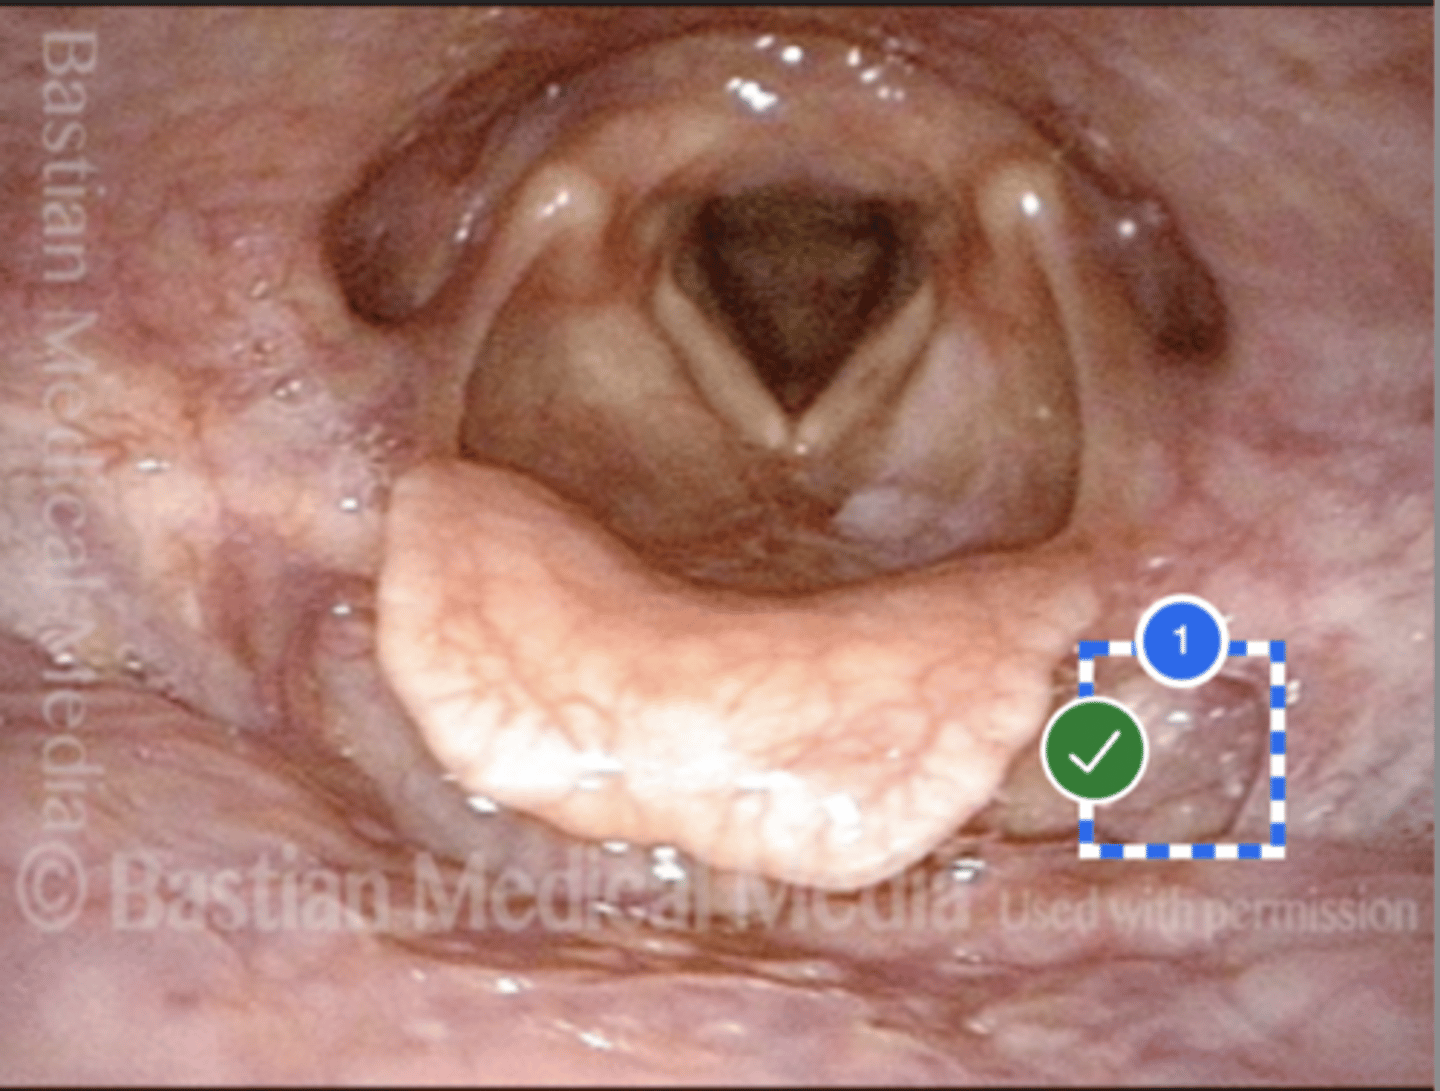

Label Right Anterior Faucial Pillar (superior view)

Label uvula (superior view)

Label palatine tonsil (superior view)

Label left true vocal fold (superior view)

Label right false vocal fold (superior view)

label right arytenoid (superior view)

Label trachea (superior view)

Label epiglottis (superior view)

Label left aryepiglottic fold (superior view)

Label laryngral surface of epiglottis (superior view)

Label lingual surface of epiglottis (superior view)

Label base of tongue (superior view)

Label right pyriform sinus (superior view)

Label upper esophageal sphincter (superior view)

Label right true vf (superior view)